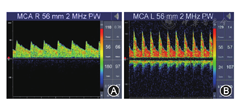

检测方法[2]:用常规方法检测ICA颅外段(4 MHz探头)及颅内Willis环主干血管(2 MHz探头),频谱以最清晰、最大血流速度取样。分析各血管的收缩期峰值流速(Vs)、平均血流速度(Vm)、舒张期末峰值流速(Vd)、频谱形态及音频改变等。一般的,(1)MCA平均血流速度(mean flow velocity of MCA,VmMCA)≥120 cm/s为CVS;(2)计算Lindegaard指数(Lindegaard index,LI),即同侧MCA与ICA颅外段(图4)Vm之比≥3为CVS[8];(3)此外,受检动脉的Vm逐日递增时,要警惕CVS的发生。